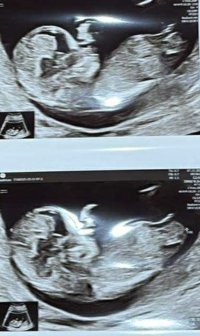

Er du gravid igjen? Sååå kjektNoen som ser noe her? 12+6![]()

Hun er såå spent på kjønnet og spurte om jeg ville legge ut ser ut som jenteNoen som ser noe her? 12+6![]()